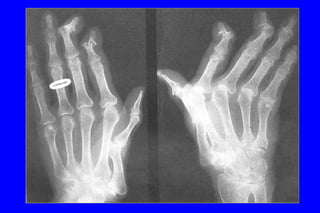

Arthrose digitaleArthrose digitale

 IPD IPPIPD IPP

 ArticulationArticulation traptrapéézozo--mméétacarpiennetacarpienne :: rhizarthroserhizarthrose

RhizarthroseRhizarthrose

 EssentiellementEssentiellement ffééminimeminime

 Le plus souvent bilatLe plus souvent bilatééralerale

 Douleur mDouleur méécanique de la base du pouce au bordcanique de la base du pouce au bord

radial de la mainradial de la main

 Douleur lancinante,Douleur lancinante, éévolution par poussvolution par poussééeses

 Manque de force, lâchage des objets, difficultManque de force, lâchage des objets, difficultéé dede

prprééhensionhension

 DouleurDouleur àà la pression de lla pression de l’’interligneinterligne articulairearticulaire

 DDééformation de lformation de l’’articulation :articulation :

adduction du 1er madduction du 1er méétacarpien,tacarpien, hyperextensionhyperextension

rrééactionnelle de lactionnelle de l’’art MP, etart MP, et flessumflessum de lde l’’art IPart IP

 Aspect de pouce en ZAspect de pouce en Z

Arthrose scapho-trapézienne

et trapézo-métacarpienne